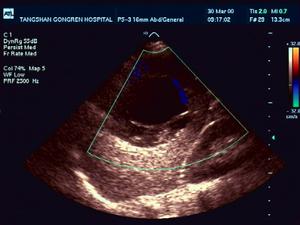

2、CT 或B 超檢查 可見包囊內有分隔結構是有活性包囊的特徵。肺部影像呈圓形包塊,CT 證實包塊內充滿液體,肝外包囊蟲病的血清學檢查陽性率低。根據包蟲囊腫的病理形態與併發症的影像特徵,結合臨床病理分類而劃分為5 型:

(1)、單髮型:由於包蟲囊內充滿水樣囊液,在B 超、CT 及MRI 成像皆呈邊緣整齊,呈現圓形或卵圓形孤立的液體占位陰影。其境界清晰、密度均勻、大小不等。一般為2~8cm,以右側及雙下肺多見。包蟲囊壁與肺組織密度差別較大,而呈現界限分明,光滑的囊壁。在較大的包蟲囊腫,其內、外囊壁間有潛在的間隙界面,可出現雙壁征。